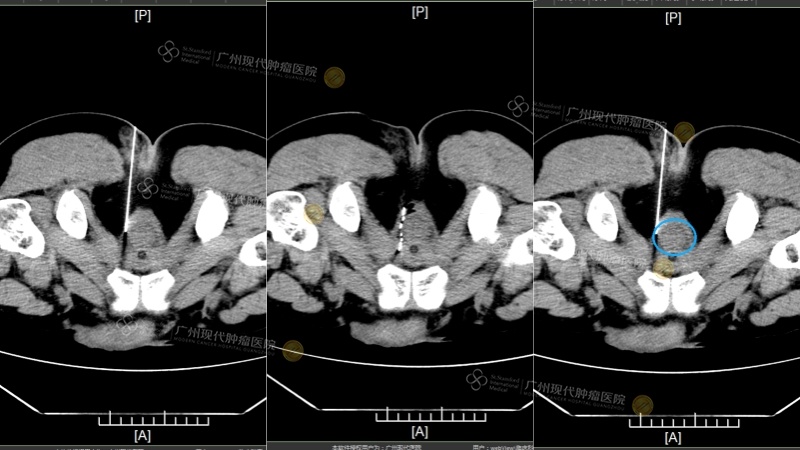

(June 2024: During particle implantation vs. after particle implantation vs. tumor location

At this point, the tumor has significantly shrunk compared to its previous size)